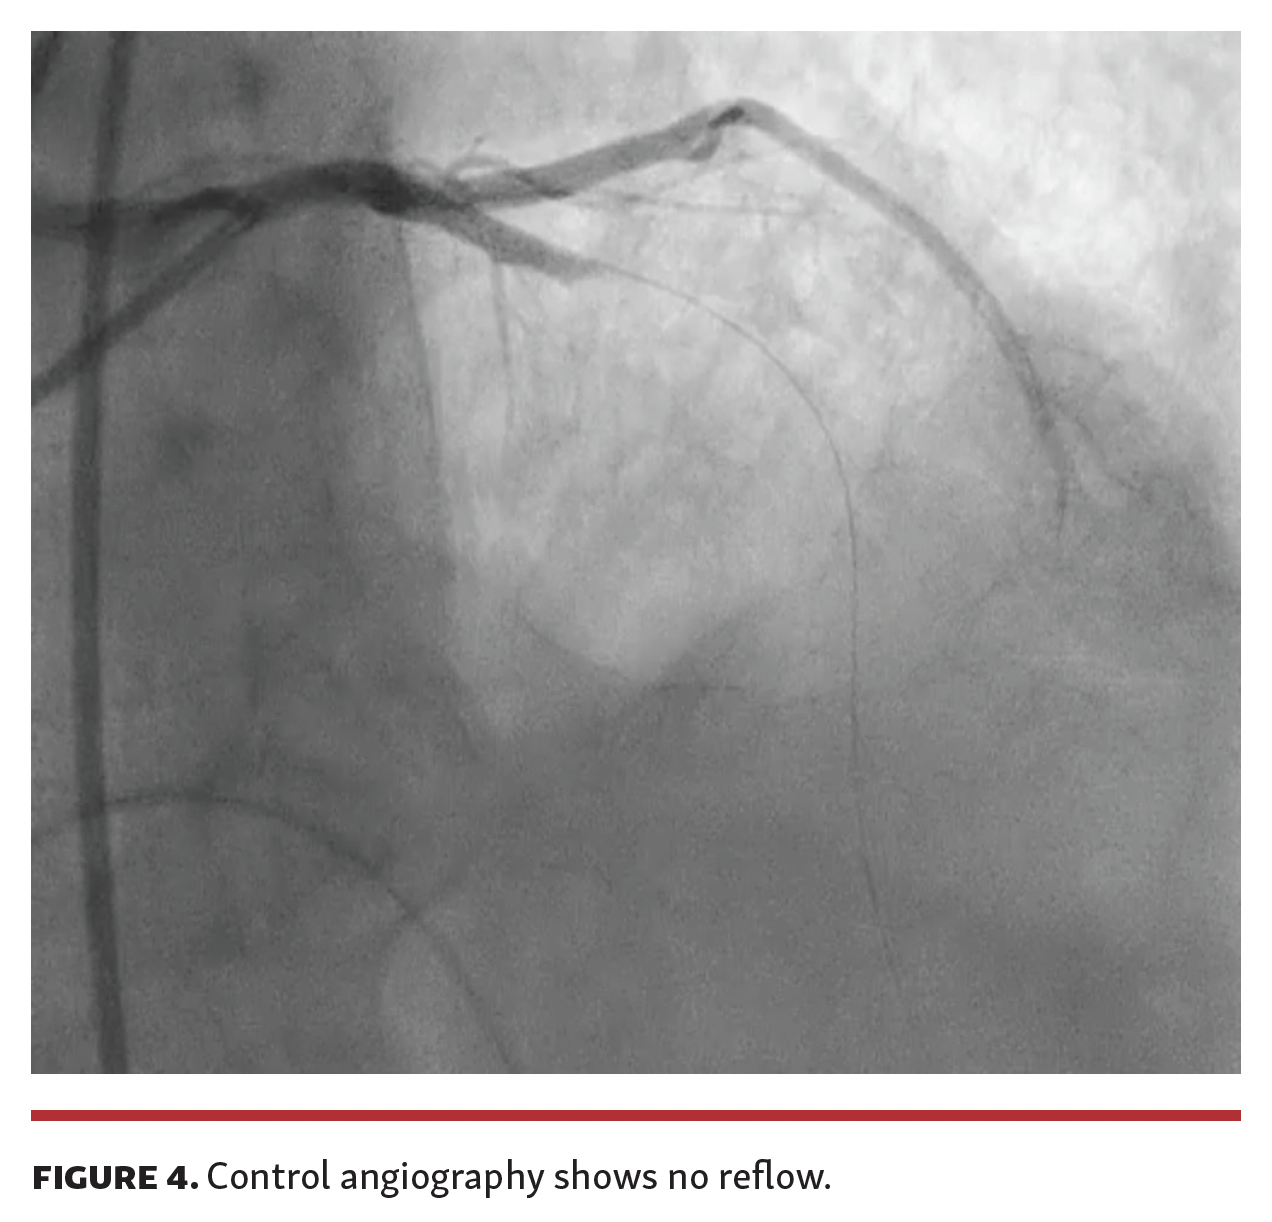

A 69-year-old male was referred to our cath lab for primary percutaneous coronary intervention (PCI) due to acute anterior ST-segment elevation myocardial infarction. The door to balloon time was about 8 hours. Left coronary angiography revealed acute occlusion of the proximal left anterior descending (LAD) artery (Figure 1 and Video 1). We immediately performed primary PCI throughout thrombus aspiration (Figure 2 and Video 2) followed by implantation of a 3 x 18 mm drug-eluting-stent (Figure 3 and Video 3). Control angiography showed no reflow (Figure 4 and Video 4). At the end of the percutaneous procedure, an abrupt clinical deterioration manifested with sudden hypotension. Transthoracic echocardiogram evidenced acute cardiac tamponade and we attempted emergency percutaneous under xiphoid pericardiocentesis. Failure to resolve cardiac tamponade and persistent hemorrhage obliged us to perform surgical subxiphoyd pericardial incision. However, the constant supply of blood from the pericardium and the development of cardiogenic shock state led us to suspect cardiac laceration. An emergency sternotomy was immediately performed.